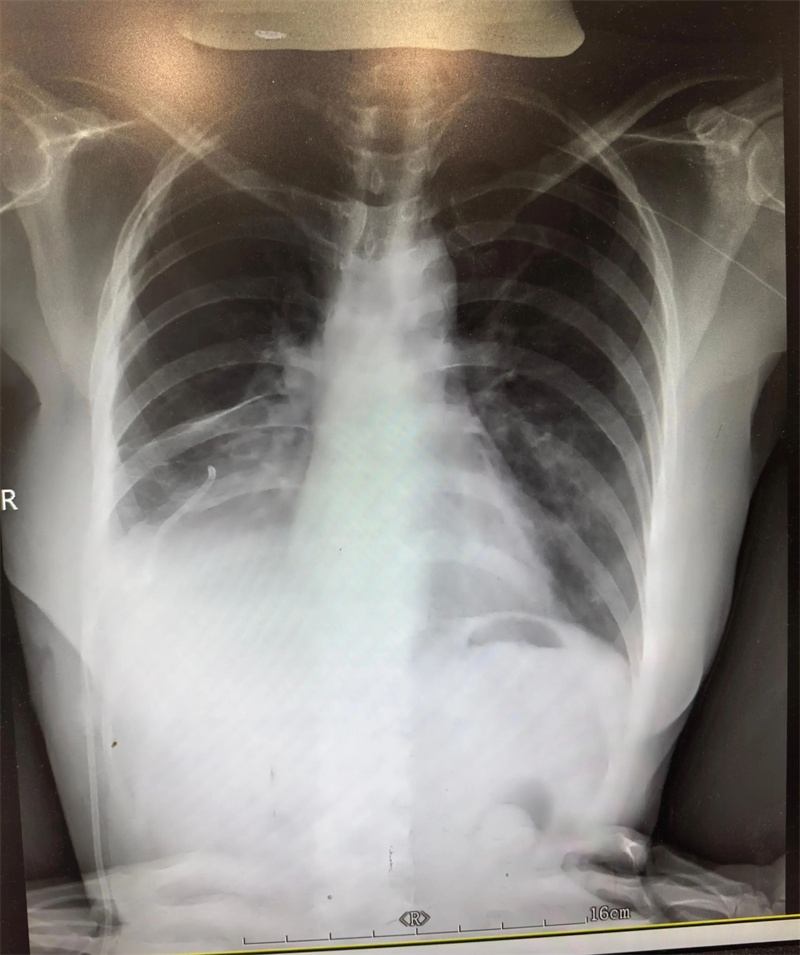

胸外科(二疗区)主任田子刚受邀参与,结合艾利影像学检查、肺功能评估及全身基础状况,与孙集思主任团队反复研讨手术指征、手术方式及围手术期风险防控要点。经过充分论证,最终确定实施“右肺下叶切除手术”。

△图片非案例所提及